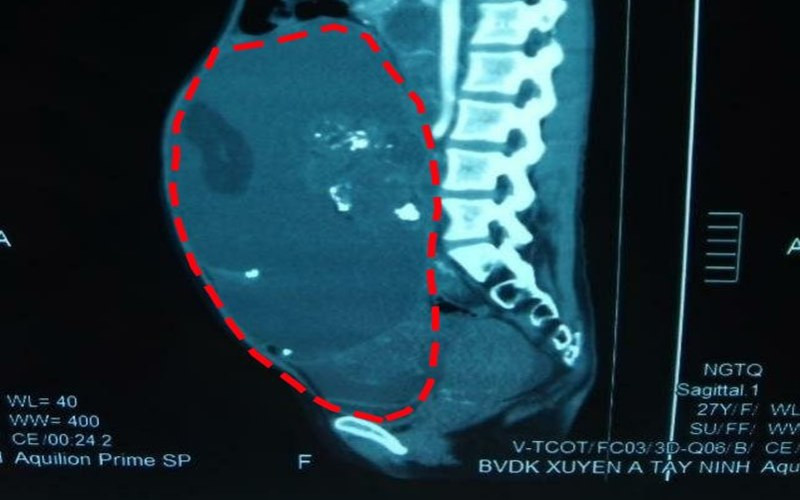

Hình ảnh khối u trước khi được bóc tách qua soi chụp. (Ảnh: Bệnh viện Xuyên Á)

Qua hội chẩn, các bác sĩ đánh giá đây là ca phẫu thuật không hề dễ dàng, khối bướu có kích thước quá to (150 x 250 x 350 mm), có dấu hiêu xâm lấn và dính vào các cấu trúc vùng chậu. Hơn nữa, các chỉ dấu về ung thư lại có kết quả tăng cao hơn bình thường. Kết luận cuối cùng buổi hội chẩn đây là trường hợp bướu quái buồng trứng tiềm năng là ác tính cao.